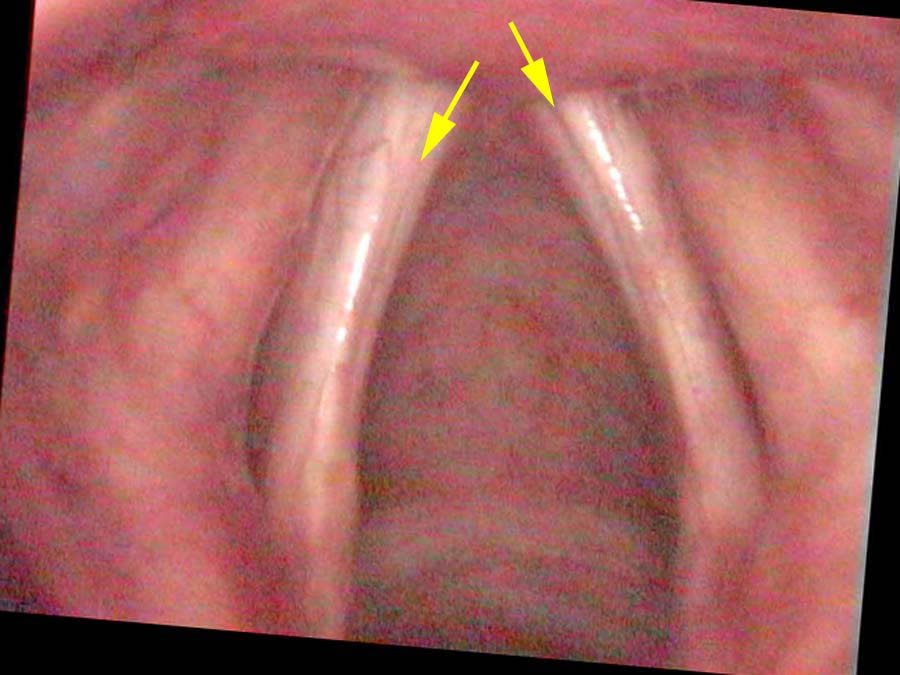

On endoscopic exam both vocal cords are bowed and very thin. There appears to be a groove running along the length of the entire vocal cord. That groove could be a scar, but seems to me to represent such significant atrophy of his vocal cord muscle or TA muscle, that the vocal ligament is the main supporting structure of the vocal cord. The mucosa appears to be draped over the ligament, then there is the groove and below that, perhaps a tiny bit of muscle.